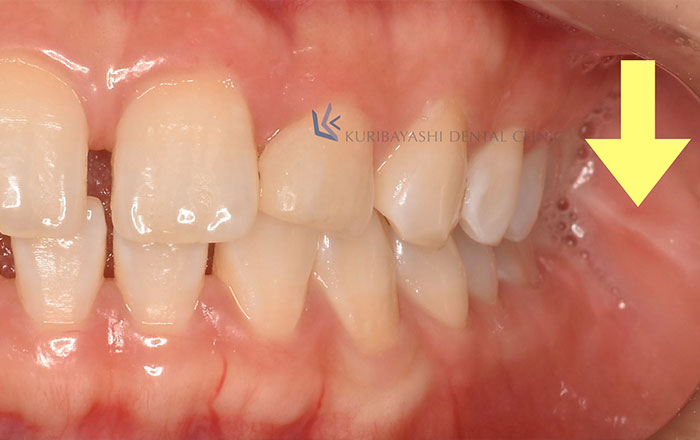

1)頬粘膜圧痕

歯ぎしり・食いしばりをしていると、頬の内側に白く線がつくことがあります。

頬の内側を噛んでしまう癖は、正式には「頬粘膜圧痕」と言います。

頬粘膜圧痕とは、歯が頬にあたってできる白い線のことです。